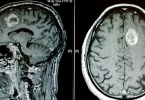

颅内动脉瘤可通过脑血管造影、CT血管成像、磁共振血管成像等方式检查。颅内动脉瘤可能与高血压、动脉硬化、外伤等因素有关,通常表现为头痛、视力模糊等症状。建议及时就医,在医生指导下选择合适的检查方式。1、脑 ...

颅内动脉瘤与脑出血的主要区别在于病因、发病机制及临床表现。颅内动脉瘤是脑血管壁的异常膨出,脑出血则是脑实质内血管破裂导致的出血。两者在危险因素、症状表现、诊断方法和治疗原则上均有显著差异。1、病因差异 ...